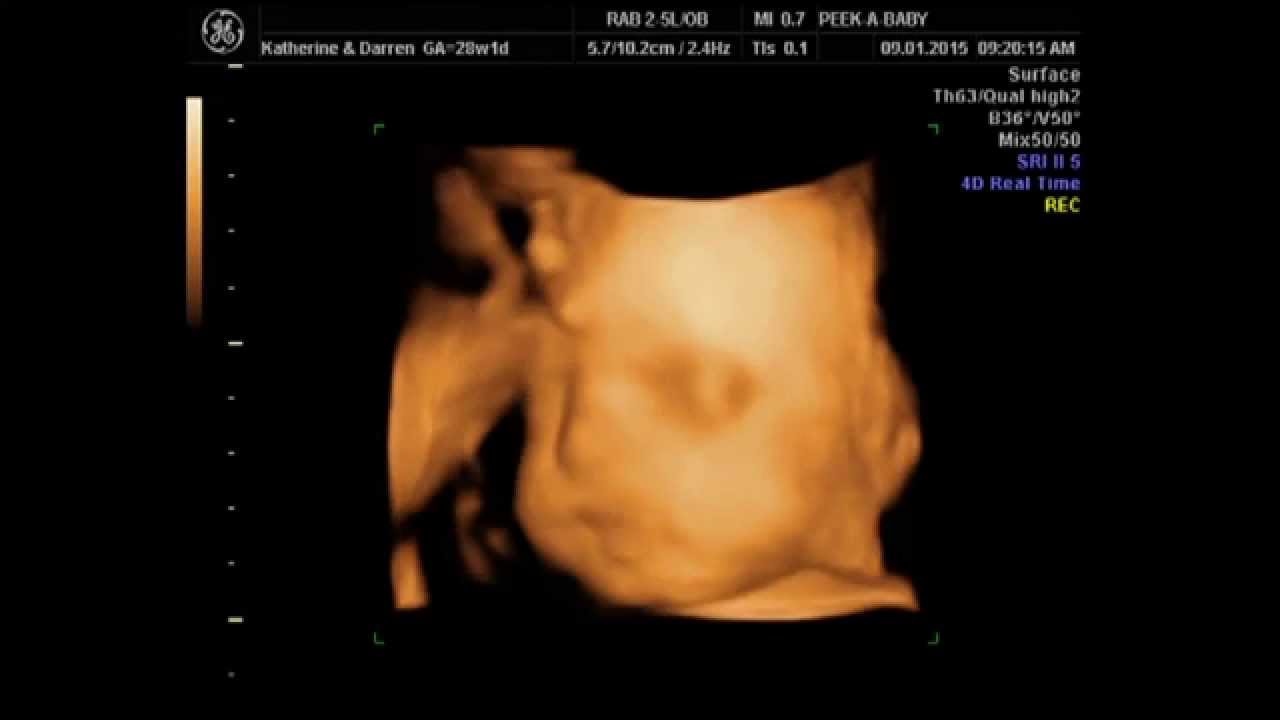

From www.youtube.com

4D Ultrasound Baby Boy Scan Charlie (28 Weeks) YouTube Baby Boy Scan Side View  An ultrasound scan is one of the most accurate ways to determine the baby’s sex. Available from 16 to 40 weeks, our gender scan will help you discover whether you’re having a boy or a girl. Ramzi discovered that using the direction or orientation of the chorionic villi (future placenta) is an accurate marker in determining. If it’s angled upward. Baby Boy Scan Side View.